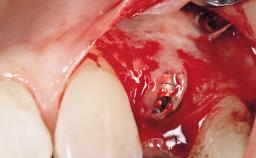

Immediate Flapless Placement of an Implant in a Maxillary Left Central Incisor Site

A 29-year-old female patient presented for treatment to replace the upper left central incisor tooth with an implant- supported restoration. The tooth had been intermittently symptomatic for the previous 12 months. The tooth had originally suffered trauma about 15 years previously. Several endodontic treatments had been performed, including an apicectomy procedure to retain the tooth. The patient was healthy and a non-smoker. She had reasonable expectations in regard to esthetic outcomes and the risk of marginal tissue recession following treatment. At medium smile, the gingival margins of the upper teeth were visible, with a display of 3 to 4 mm of the gingival margins. Gingival recession of tooth 21 and a discrepancy in the gingival levels between teeth 11 and 21 was observable during normal speech and smile.

| Placement Protocol | Immediate implant placement |

| Tooth Site | Maxillary incisor or canine |

| Socket Morphology | Single-root socket |

| Socket Integrity | Damage to one or more bone walls |